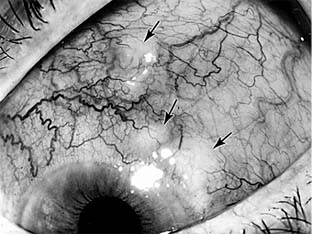

Vernal conjunctivitis characteristically affects children and adolescents; the incidence decreases sharply after the second decade of life. Like hay fever conjunctivitis, vernal conjunctivitis occurs only in the warm months of the year. Most of its victims live in hot, dry climates. The disease characteristically produces giant ("cobblestone") papillae of the tarsal conjunctiva (Figure 16-2). The keratinized epithelium from these papillae may abrade the underlying cornea, giving rise to complaints of foreign body sensation or even producing frank epithelial loss ("shield ulcer").

Figure 16-2

Figure 16-2: Giant papillae ("cobblestones") in the tarsal conjunctiva of a patient with vernal conjunctivitis.